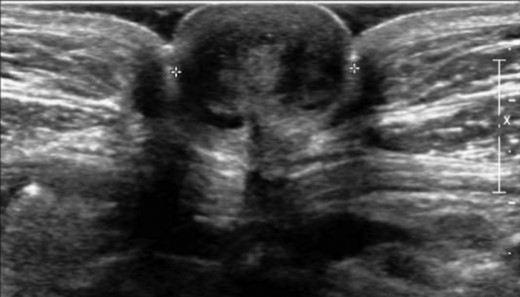

A 47-year-old healthy female presented with a painful and livid coloured nodule in the umbilicus, which gradually evolved over the past 6 months. She had no symptoms of dysmenorrhoea or cyclical umbilical pain. At physical examination, she had a soft, painful swelling with a diameter of 2 cm in the umbilicus, which was irreducible by gentle digital pressure (Fig. 1). Ultrasonography revealed a hypodense nodule of 1.8 cm at the umbilicus (Fig. 2). However, a definitive diagnosis could not be established thus far. Under the provisional clinical diagnosis, ‘irreducible umbilical hernia with probably strangulated fatty tissue in the hernia sac’ surgical exploration of the umbilicus was performed. Under general anaesthesia, a sub-umbilical incision was made. To our surprise, a subcutaneous, lobulated mass was exposed, which was fixated on the bottom of the umbilicus (Fig. 3). The abdominal wall itself was unaffected. The nodule was excised, and histopathological examination revealed connective tissue fragments with irregular tubular formations surrounded by stromal cells. Our patient was treated by excision of the swelling that turned out to be PUE. Two months after the surgery, she visited the outpatient clinic and reported complete recovery of the painful sensation and swelling in the umbilicus.

Ultrasonography of the umbilicus demonstrated a hypodense nodule of 1.8 cm in the umbilicus.